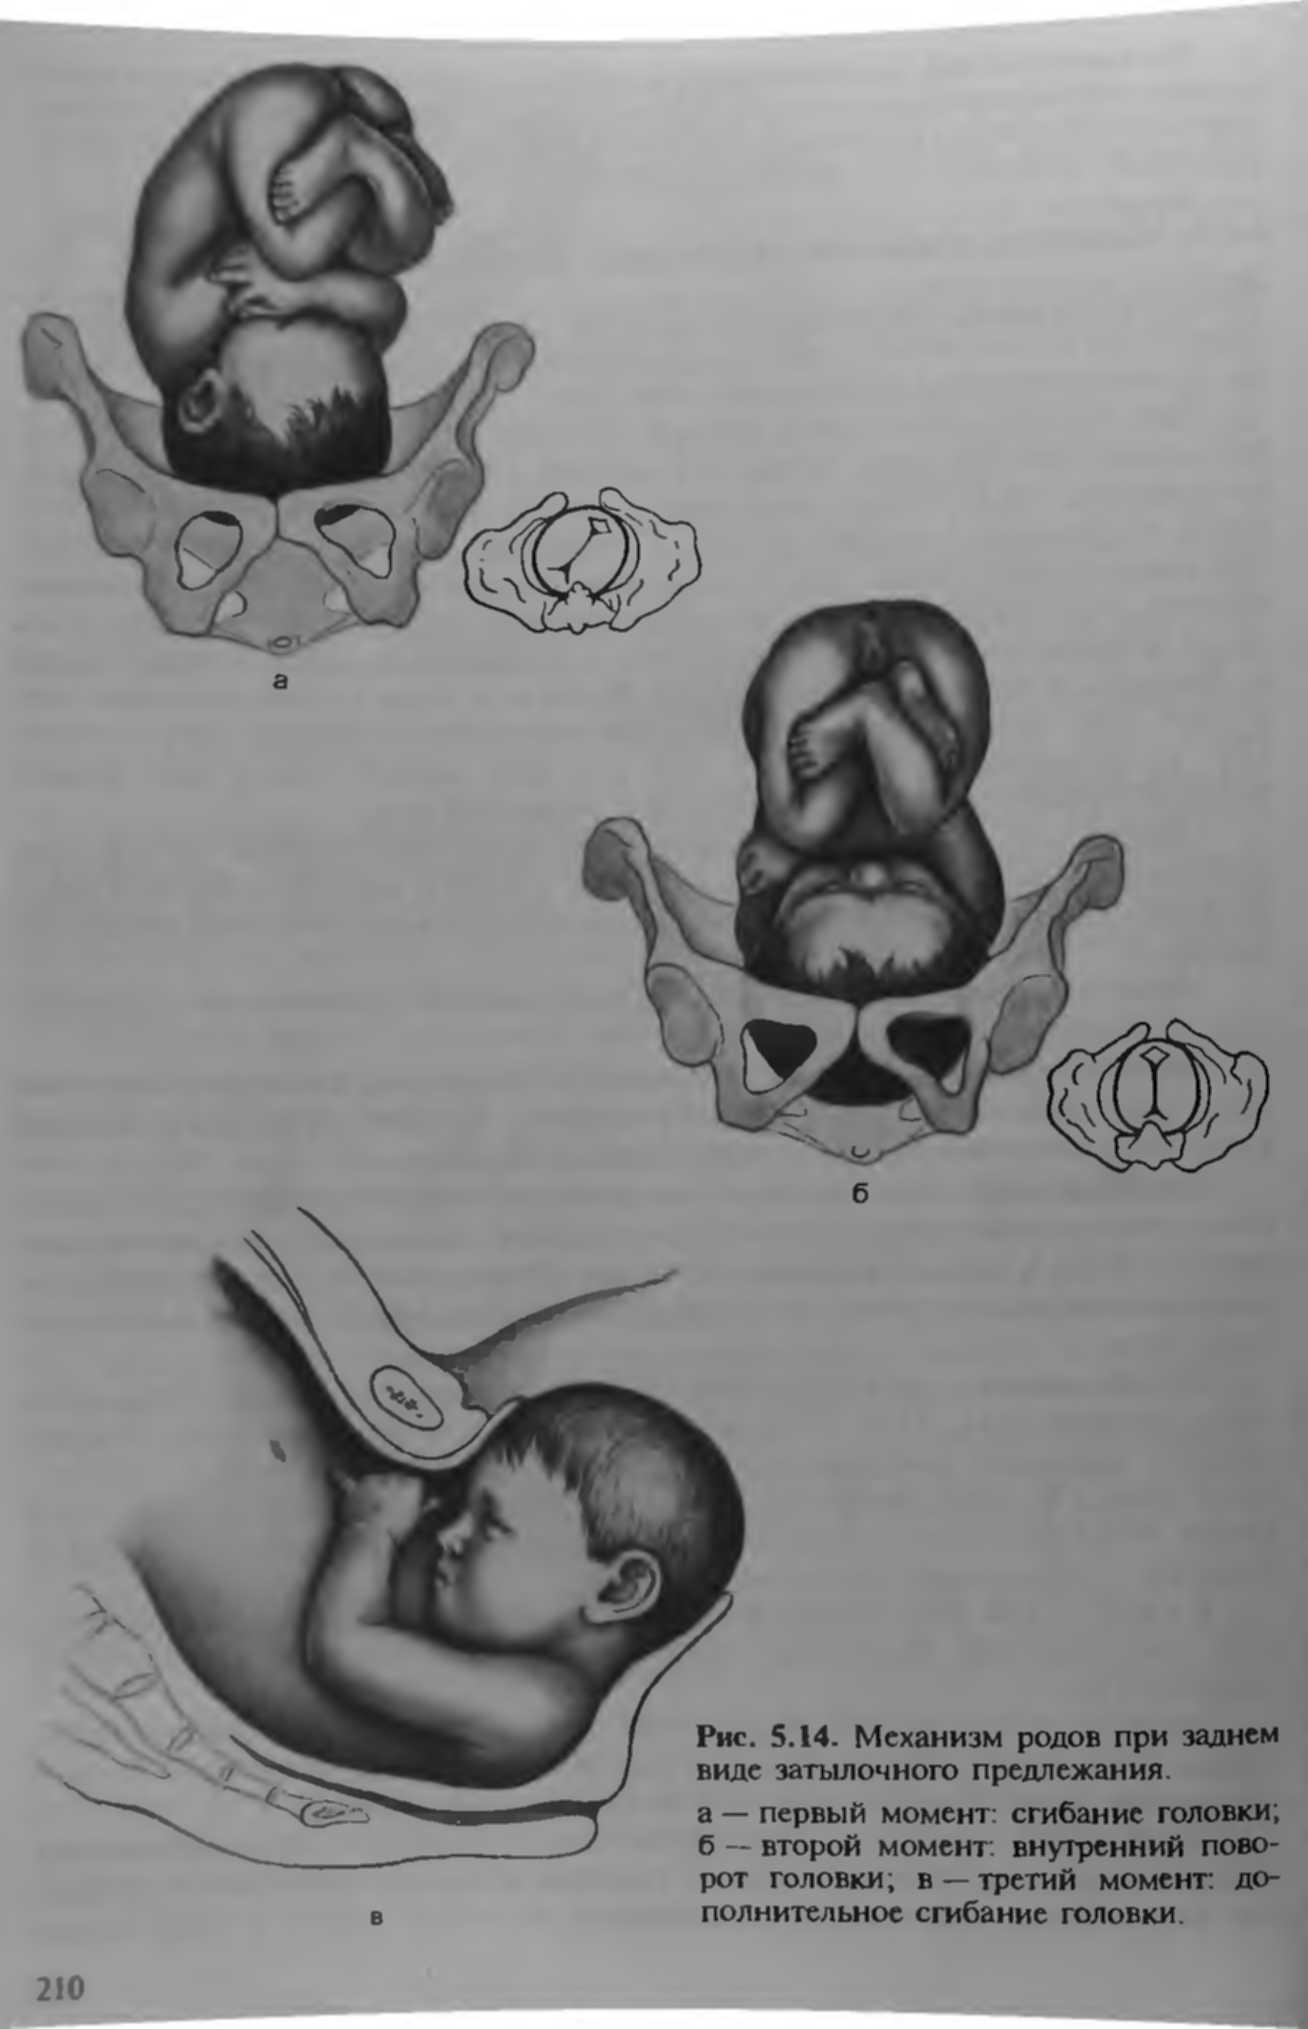

Задний вид затылочного предлежания биомеханизм родов

1 Позиция задний вид затылочного предлежания